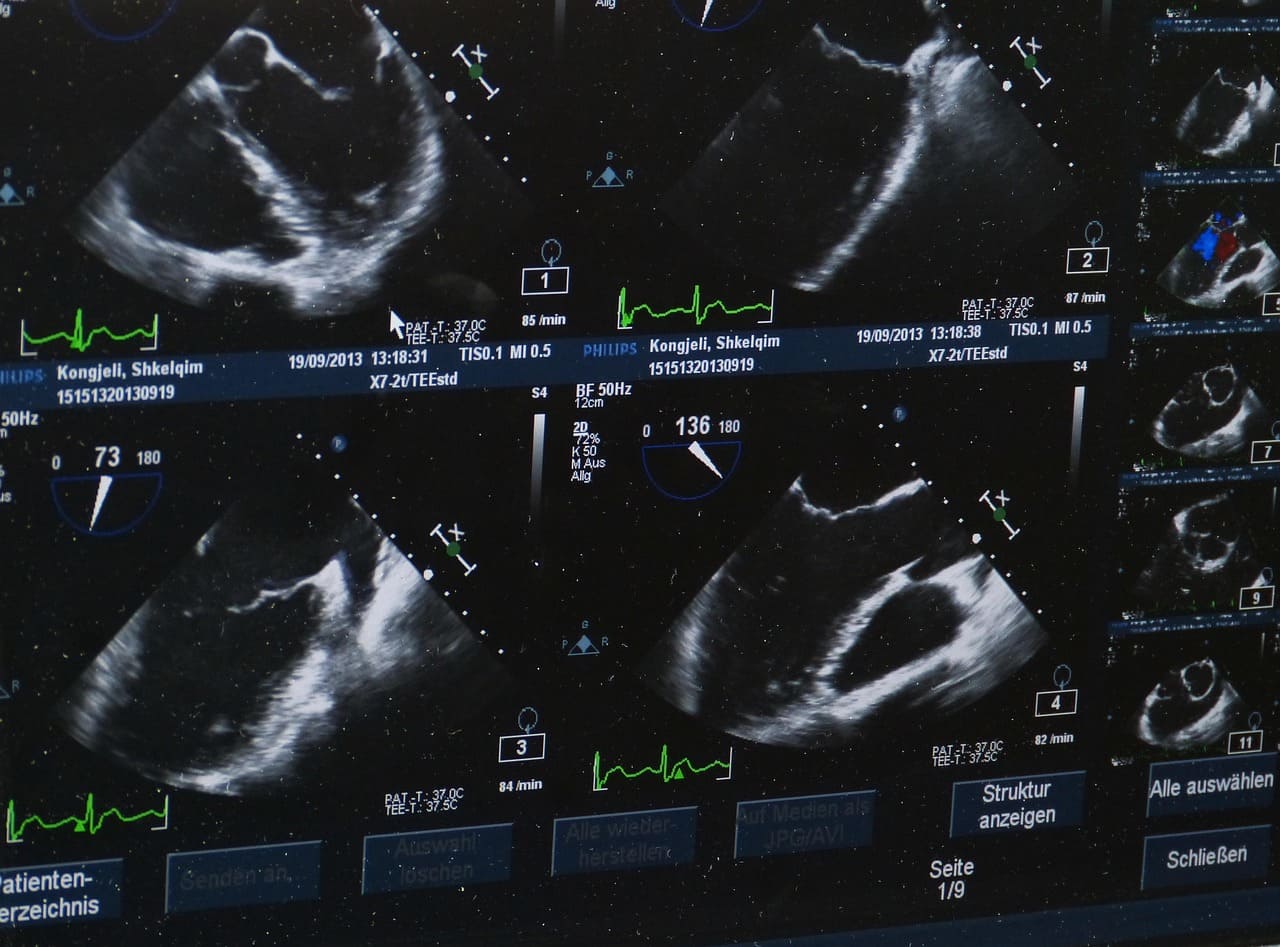

Dans le domaine médical moderne, l’échographie se révèle indispensable en gynécologie. En offrant des diagnostics précis et immédiats, cet examen non invasif améliore la prise en charge des patientes. Opter pour un échographe, comme ceux de la marque Sonoscanner, représente un investissement stratégique pour l’efficacité de votre cabinet.

Des diagnostics plus précis et immédiats

La puissance de l’échographe réside dans sa capacité à fournir, en temps réel, une image fidèle de l’appareil génital féminin. Lorsqu’un kyste ovarien est suspecté, l’état de la muqueuse utérine interrogé, ou la viabilité fœtale évaluée, la vision directe fournie par la sonde endovaginale ou transabdominale est indispensable. Cette précision immédiate :

• Réduit considérablement les erreurs de diagnostic.

• Permet d’ajuster le traitement dès la première consultation.

• Sécurise la patiente, notamment lors du suivi de grossesse, où l’absence de rayons X est un gage de tranquillité.